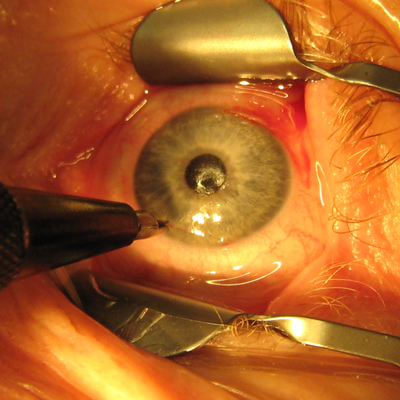

Stephanie Chen, MD, dove into the cost and waste reduction achieved from transitioning to a reusable phaco platform and reusable diamond knives, from her recent study published in JCRS. Dr. Chen also discussed the multisociety position paper published in JCRS advocating for access to multiuse phaco cassettes.